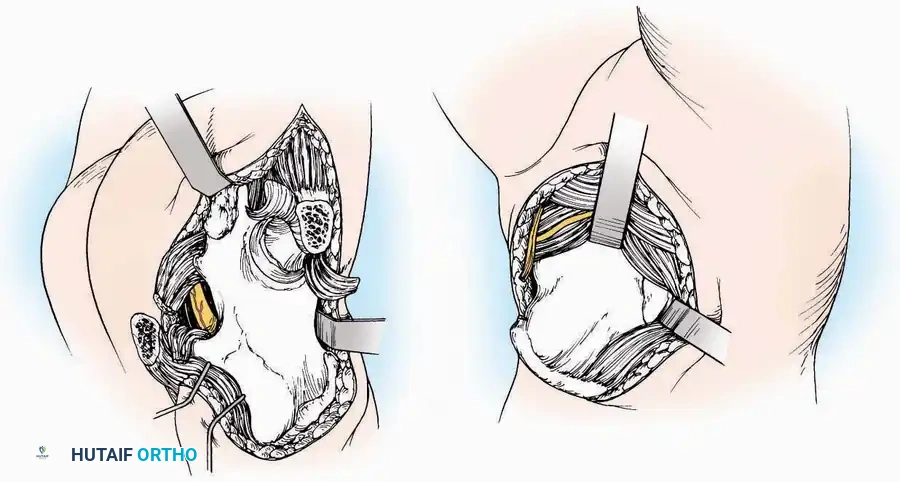

Anterolateral Approach

The anterolateral approach is widely considered the "universal incision" for the foot and ankle. It provides unparalleled access to the ankle joint, the talus, and the majority of the tarsal articulations, while safely avoiding the major anterior neurovascular bundle. The only tarsal joints inaccessible via this route are the naviculocuneiform joints (specifically the medial and intermediate).

Indications: Total talectomy, triple arthrodesis, ankle arthrodesis, and open reduction of complex talar neck fractures.

Surgical Technique:

* Incision: Begin over the anterolateral aspect of the leg, medial to the fibula and 5 cm proximal to the ankle joint line. Carry it distally over the joint, crossing the anterolateral aspect of the talar body and the calcaneocuboid joint, terminating at the base of the fourth metatarsal.

* Superficial Dissection: Incise the superficial fascia and the superior and inferior extensor retinacula down to the periosteum of the tibia and the ankle joint capsule.

* Vascular Ligation: This trajectory usually requires the identification and ligation of the anterolateral malleolar and lateral tarsal arteries.

* Nerve Protection: Retract the skin edges carefully. Identify and protect the intermediate dorsal cutaneous branches of the superficial peroneal nerve (SPN), which frequently cross the distal aspect of this incision.

* Muscle Management: Identify the origin of the extensor digitorum brevis (EDB) muscle on the lateral calcaneus. Divide it in the direction of its fibers, or detach its origin entirely and reflect it distally to expose the subtalar and calcaneocuboid joints.

* Deep Exposure: Retract the extensor digitorum longus (EDL) tendons, the dorsalis pedis artery, and the deep peroneal nerve (DPN) medially. Incise the anterior ankle capsule to expose the tibiotalar joint.

* Tarsal Exposure: Expose the talonavicular joint by dissecting deep to the extensor tendons and incising its capsule transversely. Continue laterally through the capsule of the calcaneocuboid joint. By excising the fat pad within the sinus tarsi (lateral and inferior to the talar neck), the posterior facet of the subtalar joint is brought into direct view.